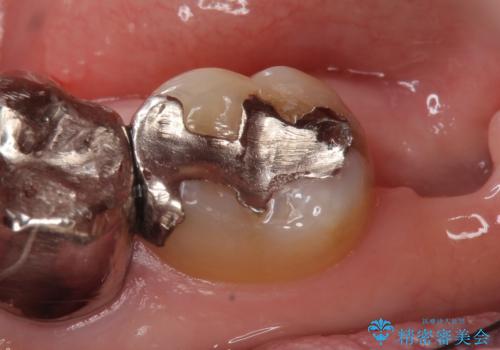

- 冷たいものを飲むと右下の奥歯が痛むので診て欲しいといらっしゃった方の症例です。

銀歯及び虫歯を除去後、より適合の良いPGA(ゴールド)インレーによる修復を行いました。